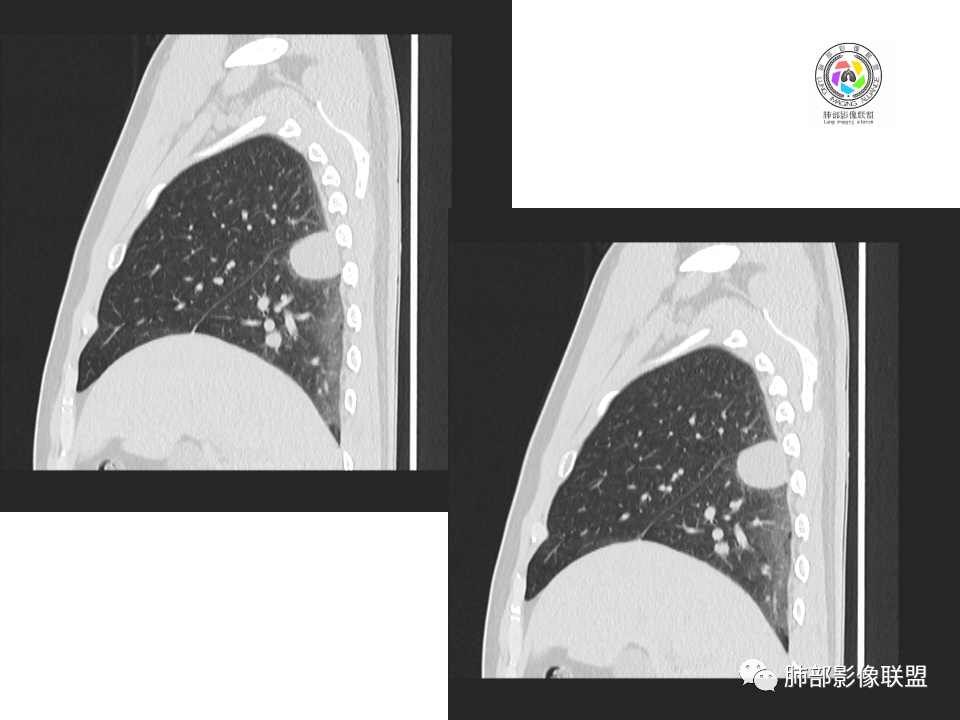

中年男性,20余年吸烟史,体检发现,右肺下叶胸膜下软组织肿块,边界清楚,边缘平直,有压迹,密度均匀,增强强化不明显,未见坏死区,考虑良性可能,炎性肉芽肿?。右肺下叶一小结节影,多个层面均有,考虑整体呈管状,走行与支气管相似,增强强化不明显,支气管来源可能,粘液栓?右肺中叶外周见斑点状、小结节状影,炎性病变?一元论,支气管来源病变,支气管囊肿?粘液栓?阻塞性炎症?长期吸烟史,鳞癌不除外。

中年男性,体检发现占位。右肺下叶背段胸膜下肿块,周围晕征,有小分叶,与支气管、肺内血管关系不清,形似山丘,重建可见肿块呈D字形凸向肺部。似跨斜裂,似有小凸起与肋下缘相连,增强似有轻微均匀强化。右肺下叶外基底段小结节,位于血管周围,部分边缘平直,轻微均匀强化。考虑二元:一、右下叶背段肿块为肺外病变,神经鞘瘤?SFT?鉴别小细胞癌、隐球菌病;二、右下叶外基底段结节考虑为良性结节、炎性肉芽肿?

2.右肺下叶背段胸膜下块影,边界清楚光整,上下极见磨玻璃晕,未见明显分叶毛刺和棘状突起,未见胸膜凹陷或胸壁侵入。密度均匀,轻度不均匀强化。未见支气管进入。

3.右肺中叶外侧段胸膜下散在小片影,磨玻璃密度为主,边界不清,支气管相关。符合炎性特征!

4.右肺下叶基底段支气管血管束旁小结节影,边界清楚,强化不明显。注意,这结节在“遥远的”基底段。